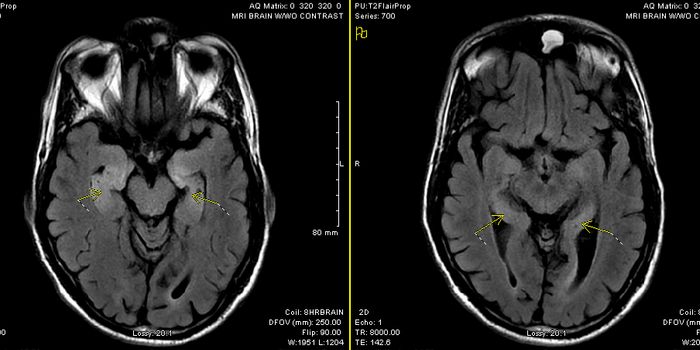

AUG 12, 2020NeuroscienceMany COVID-19 patients experience neurological symptoms. These include loss of smell and delirium, with some reporting l ...